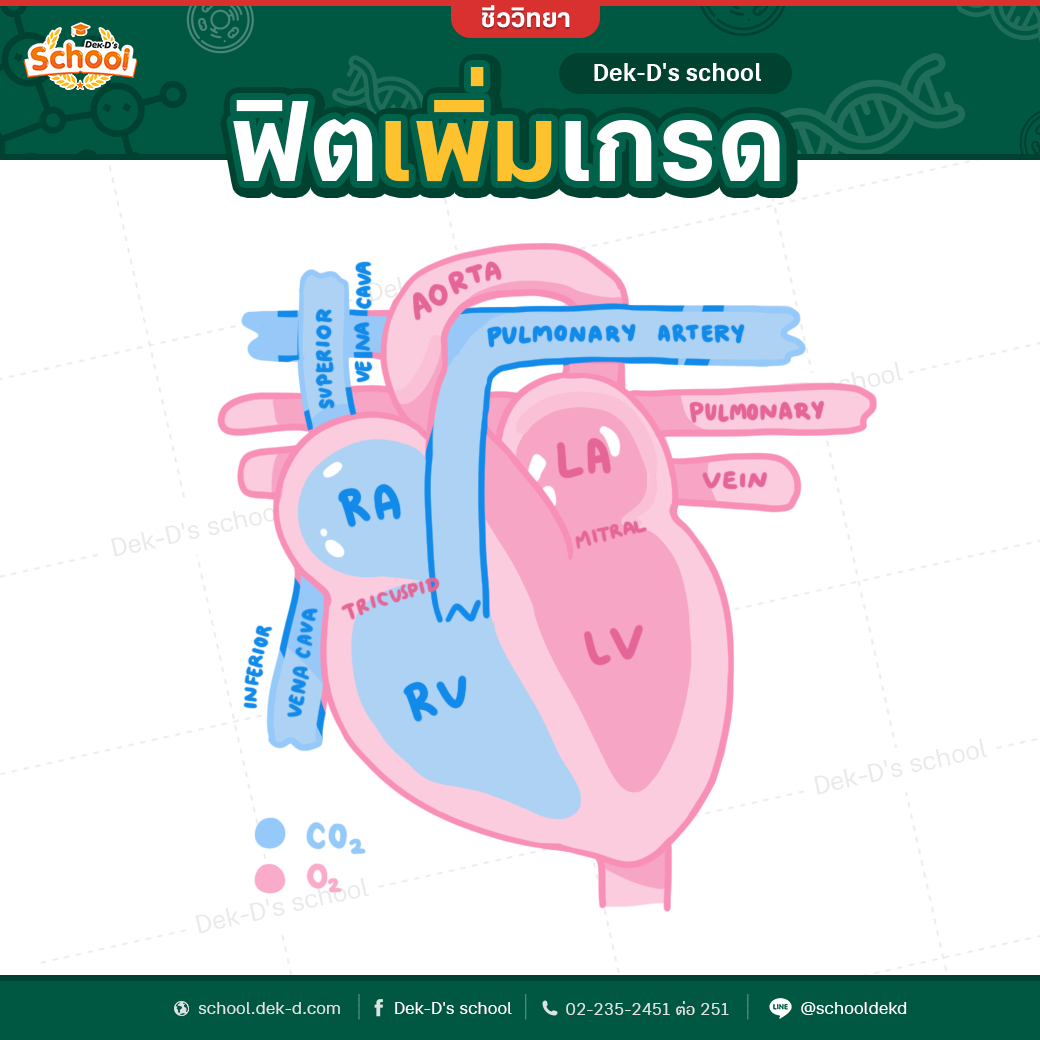

37,900+ การไหลเวียนของเลือด ภาพถ่ายสต็อก รูปภาพ และภาพปลอดค่าลิขสิทธิ์ … หัวใจกับการไหลเวียนของเลือด – ระบบไหลเวียนโลหิต

หัวใจกับการไหลเวียนของเลือด – ระบบไหลเวียนโลหิต ม.2 ระบบหมุนเวียนเลือด | Science – Quizizz

ม.2 ระบบหมุนเวียนเลือด | Science – Quizizz ระบบไหลเวียนเลือด: หัวใจ

ระบบไหลเวียนเลือด: หัวใจ รูปภาพประกอบระบบไหลเวียนโลหิตของร่างกายที่วาดด้วยมือ PNG , ร่างกาย …

ฟิตเพิ่มเกรด ชีวะ ม.ปลาย – หัวใจเเละระบบหมุนเวียนเลือด – Dek-D’s School ระบบไหลเวียนเลือด 5/5 พ.พ. – Posts | Facebook